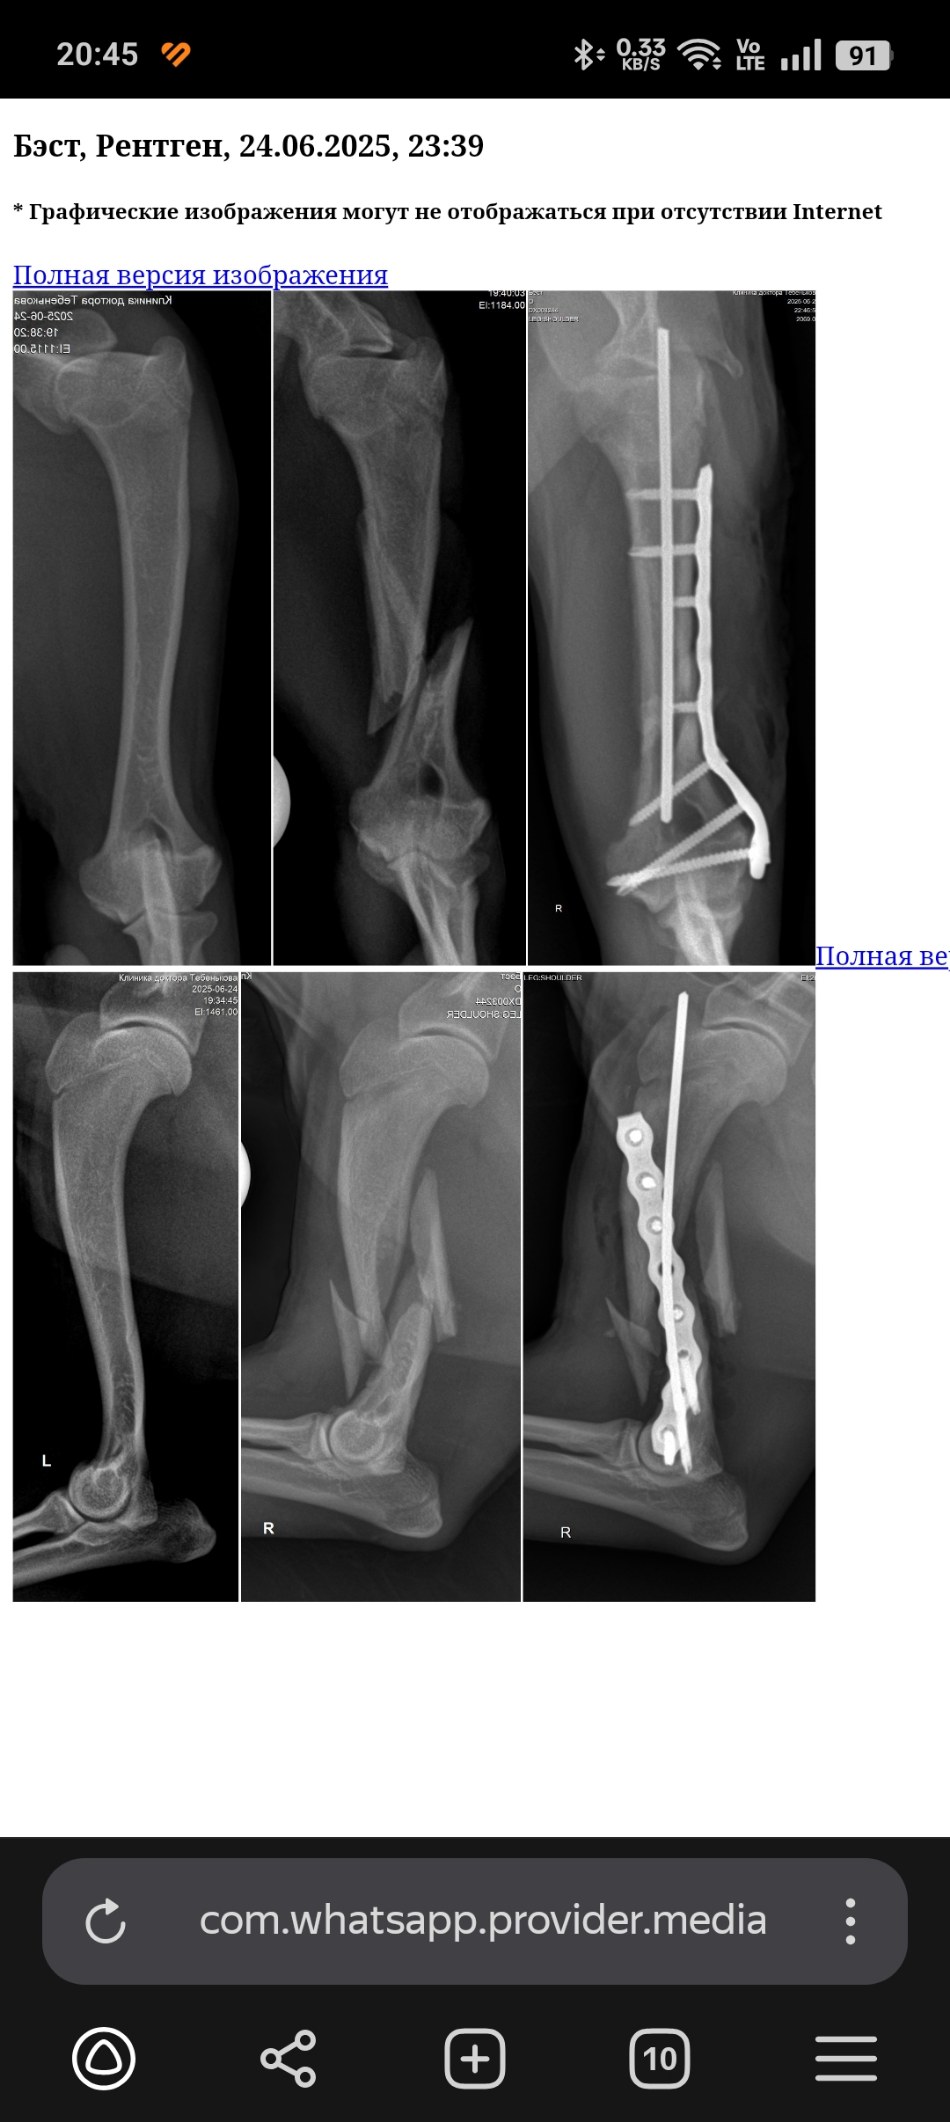

Найден с переломом плеча.

Рентген до и после

Screenshot_2025-06-25-20-45-40-45_21da60175e70af211acc4f26191b7a77.jpg